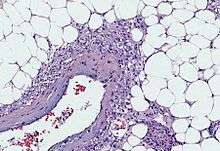

An angiomyolipoma is composed of varying proportions of vascular cells, immature smooth muscle cells and fat cells.[2] These three components respectively give rise to the components of the name: angio-, myo- and lip-. The -oma suffix indicates a tumour.